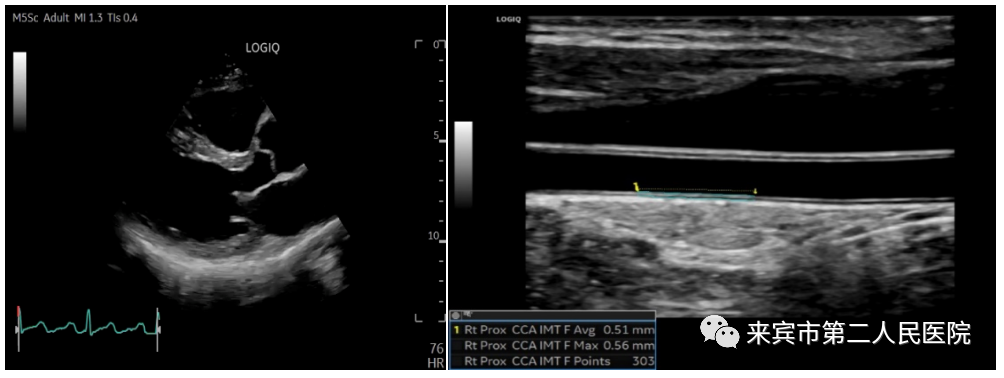

二、彩超在血管检查中的应用:

彩超可以对人体的颅内外动静脉,心血管以及四肢动静脉进行检查,应用彩色多普勒可以检测到颅内血管内血流速度,以此判断有无血管痉挛或者是血管狭窄。

通过对颈部血管的检测,可以清晰地显示出颈部动脉壁是否增厚、斑块、血栓、狭窄、闭塞等等,而通过对四肢血管检测,可以检查出动脉有无狭窄、闭塞以及血流的速度,可以排除四肢静脉有无血栓形成,以及有无瓣膜功能不全、反流等等情况。